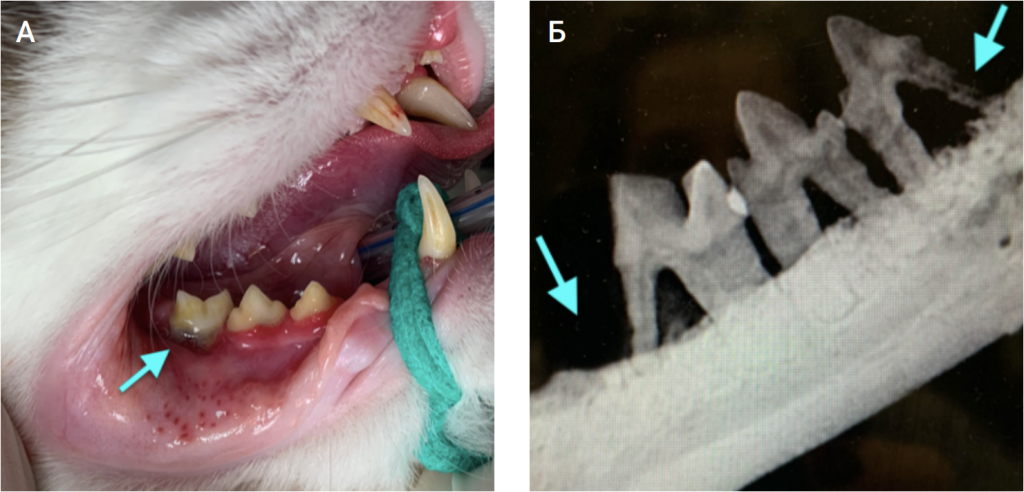

Обязательным инструментом для установления правильного и точного диагноза должна быть комплексная клиническая диагностика пациента2,3:- визуальный осмотр (фото 9 -11 – пациенты с явной резорбцией зубов);

- инструментальный осмотр (зондирование/зеркальный осмотр; фото 12, 13);

В процессе осмотра у кошек (без седации) часто выявляется резорбция зубов, проявляющаяся следующим образом: область отсутствующего вещества зуба, отсутствие коронки зуба (неполный зубной ряд), десневые бугорки, локальный гингивит, изменение цвета зубов (они практически прозрачные, а цвет коронки зуба розовый), кровоточивость десен, минерализованные зубные отложения (часто располагаются в области разрушенных зубов) и пр.

Общая анестезия необходима для удаления зубных отложений, инструментального осмотра тканей зуба, пародонта и рентгенологического исследования. Стоматологический зонд используется для зондирования дефектов или углублений в цементно-эмалевой границе и десне. Должны быть исследованы все поверхности каждого зуба и пародонта.